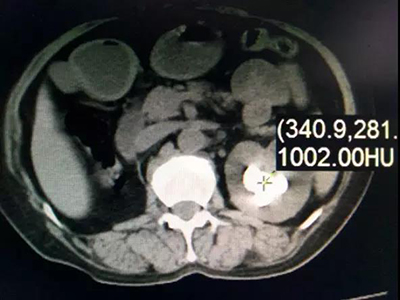

入院后彩超檢查顯示:左腎竇內(nèi)可見數(shù)個大小不等的結(jié)石,最大的2.6 x1.9厘米,左輸尿管上段距腎門2.5厘米處可見一大小約1.9厘米的結(jié)石。腎盂靜脈造影顯示:左腎及左側(cè)輸尿管上段多發(fā)結(jié)石,伴左側(cè)腎盂、腎盞擴張;右腎缺如。CT檢查顯示:左腎腎盂、腎盞多發(fā)不規(guī)則高密度影,部分形成腎盞鑄型,邊緣銳利,CT值780—1500HU,左腎多發(fā)類圓形低密度影,右腎缺如。心電圖檢查:T波改變。胸片提示:兩肺紋理增多、心影增大。經(jīng)詳細檢查最終確診為:左腎多發(fā)結(jié)石、左輸尿管多發(fā)結(jié)石、左腎多囊腎、右腎缺如、高血壓Ⅱ級。